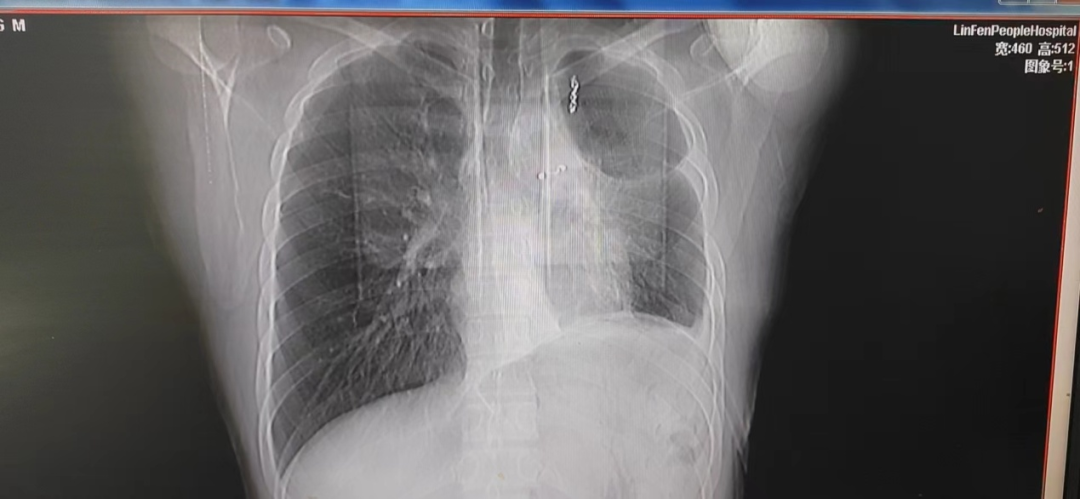

术后早期胸片,见左上胸腔较大的残腔